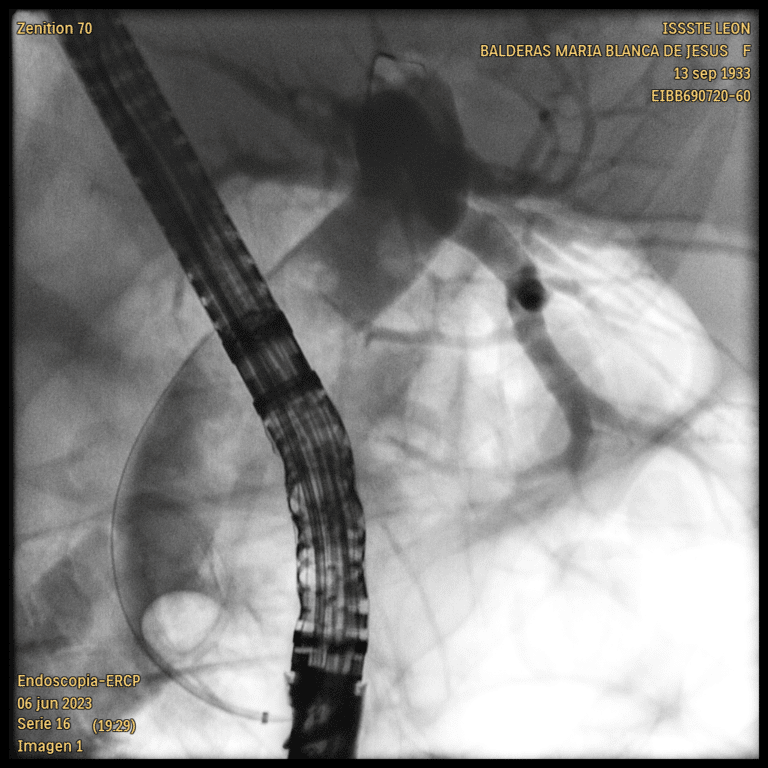

CPRE cerca de Querétaro – Manejo Especializado de Enfermedades Biliares y Pancreáticas La Colangiopancreatografía Retrógrada Endoscópica (CPRE) es un procedimiento terapéutico esencial para el manejo de patologías como la coledocolitiasis, pancreatitis biliar, estenosis de la vía biliar, ictericia obstructiva y…